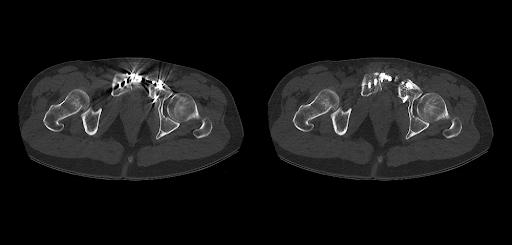

Технология SEMAR (Single Energy Metal Artifact Reduction) позволяет снизить количество артефактов от металлических конструкций, что особенно важно при исследовании позвоночника.